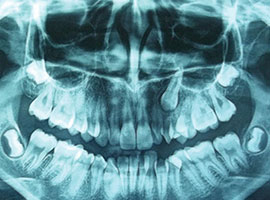

Extraction or Non Extraction?

This orthodontist needs help treatment planning this case - a mixture of Class I and II issues, including impactions. How would you write up the plan for this case?